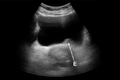

- Stones

- Bladder bulge may indicated a UVJ stone[2]

- Free fluid

- Anechoic (black) fluid outside the bladder is suggestive of free fluid

- Look for 'pointy edges' which increases suspicion for fluid not in another structure (cyst, ovary, bowel, etc)